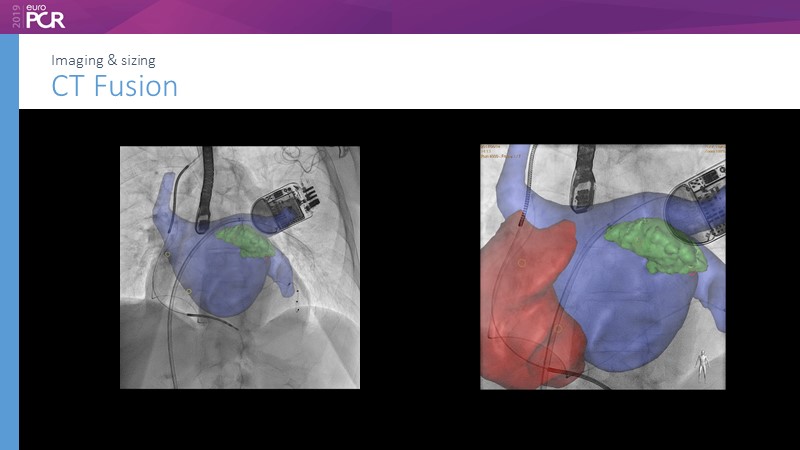

Pre-procedure planning

Previous Next